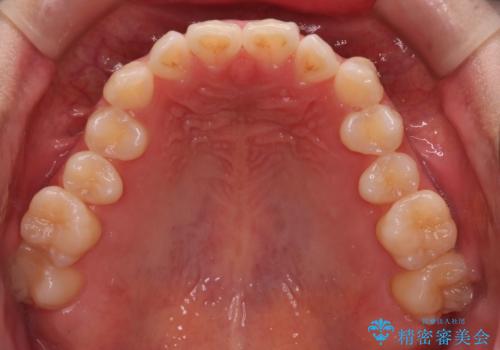

最初は、一番後ろの奥歯でしか噛んでいない状態で、上下の前歯の先端がちょうど当たる切端咬合でした。

口腔習癖の改善及び、ワイヤー矯正にて歯列の平坦化を行うことで咬合を確立することができました。